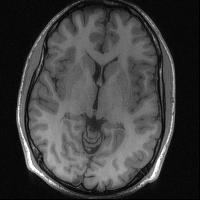

Magnetic resonance imaging serves as an essential tool for clinical diagnosis. However, it suffers from a long acquisition time. The utilization of deep learning, especially the deep generative models, offers aggressive acceleration and better reconstruction in magnetic resonance imaging. Nevertheless, learning the data distribution as prior knowledge and reconstructing the image from limited data remains challenging. In this work, we propose a novel Hankel-k-space generative model (HKGM), which can generate samples from a training set of as little as one k-space data. At the prior learning stage, we first construct a large Hankel matrix from k-space data, then extract multiple structured k-space patches from the large Hankel matrix to capture the internal distribution among different patches. Extracting patches from a Hankel matrix enables the generative model to be learned from redundant and low-rank data space. At the iterative reconstruction stage, it is observed that the desired solution obeys the learned prior knowledge. The intermediate reconstruction solution is updated by taking it as the input of the generative model. The updated result is then alternatively operated by imposing low-rank penalty on its Hankel matrix and data consistency con-strain on the measurement data. Experimental results confirmed that the internal statistics of patches within a single k-space data carry enough information for learning a powerful generative model and provide state-of-the-art reconstruction.